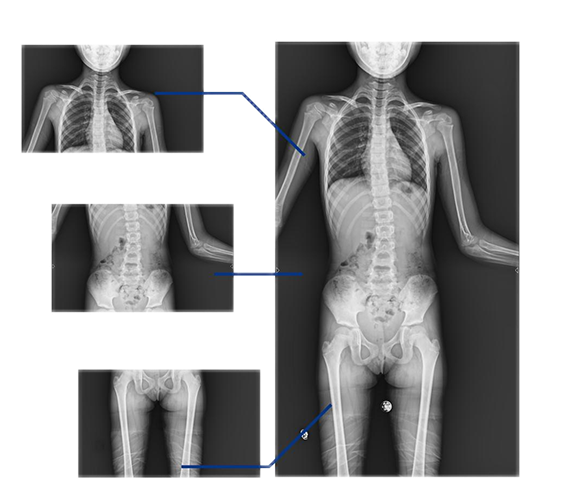

同時,動態(tài)DRF的全景拼接技術(shù)能夠輔助脊柱畸形矯形治療、康復(fù)檢查,為臨床提供高精度圖像。該技術(shù)可自動或手動拼接,圖像無拼接痕跡,全脊柱重組影像準(zhǔn)確率高、結(jié)構(gòu)清晰。在脊柱側(cè)彎患者的康復(fù)治療中,拼接技術(shù)的應(yīng)用還有助于臨床對患者的脊柱整體形態(tài)、病變程度等進(jìn)行全面而直觀地掌握,為后續(xù)的治療提供良好的支持。